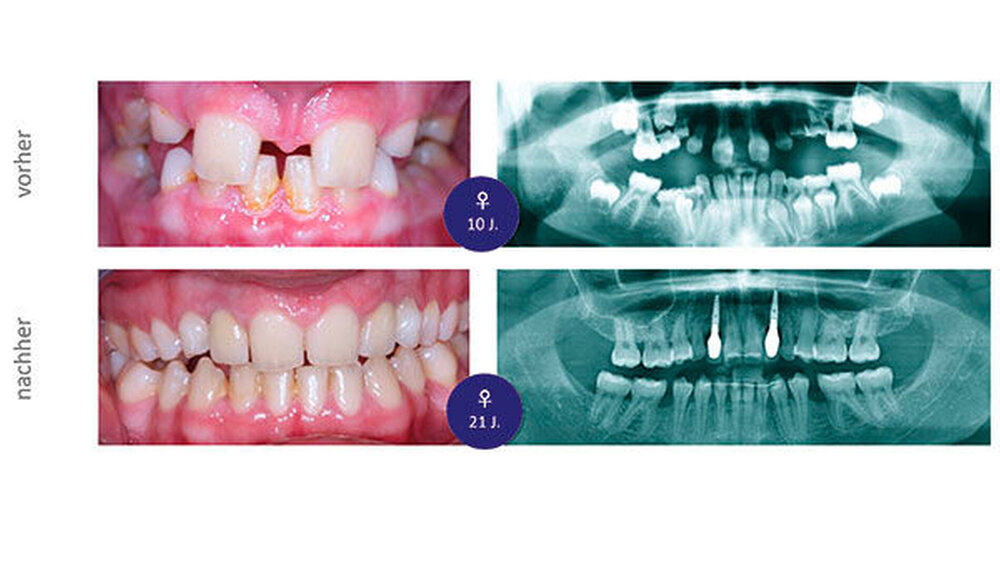

Die zehnjährige Patientin wurde uns von der Kieferorthopädin zur Wertung möglicher chirurgischer Maßnahmen bei insgesamt acht Nichtanlagen (Abbildung 1a bis c) vorgestellt. Im OPG stellt sich das Fehlen von drei permanenten Zähnen im I. Quadranten, von vier im II. Quadranten und einem im III. Quadranten dar (Abbildung 1c). Aufgrund des noch jungen Alters der Patientin zum Zeitpunkt der Erstvorstellung und des damit noch verbundenen Vorhandenseins der Milcheckzähne 73 und 83 entschieden wir uns für das folgende kieferorthopädisch-kieferchirurgische Vorgehen (Abbildung 2):

Im Alter von nunmehr 21 Jahren, also elf Jahre nach Milchzahn- und Prämolaren-Transplantation, kam es zu einer klinischen Lockerung der Milchzahn-Transplantate, weswegen unverzüglich eine implantologische Versorgung in regio 12 und 22 eingeleitet wurde. Bei der Extraktion der gelockerten Milchzähne erfolgten alveolarplastische Maßnahmen mit Auffüllung der Extraktionswunden mit Knochenersatzmaterial. Die Implantate wurden acht Wochen nach Alveoloplastik inseriert, die prothetische Versorgung erfolgte 2,5 Monate später (Abbildung 7). Ohne größeren chirurgischen Aufwand konnte ein ästhetisch ansprechendes periimplantäres Lagergewebe geschaffen werden. Die erreichte klinische Bisshebung (Abbildung 7a) kann unter Berücksichtigung des ursprünglichen Fehlens von insgesamt sieben Zähnen im Oberkiefer als sehr zufriedenstellend angesehen werden. Eine weitere Verbesserung der ästhetischen Situation kann im Rahmen der noch notwendig werdenden implantologisch-prothetischen Versorgung erfolgen.